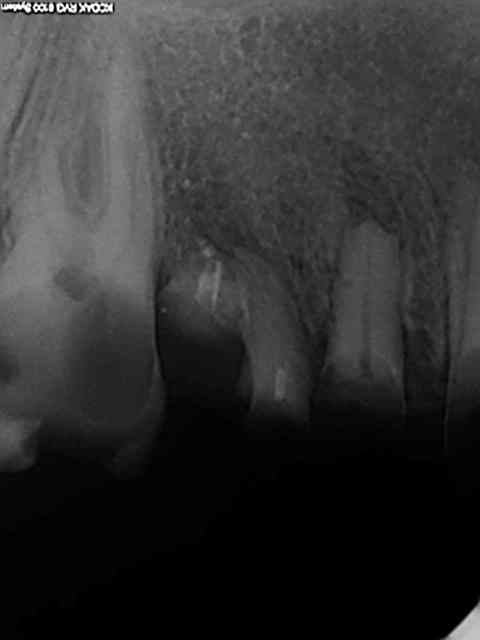

Comme celle là par exemple ? 20 ans et presque toutes ses dents )))) Mieux vaut avoir les radios initiales par les temps qui courent !